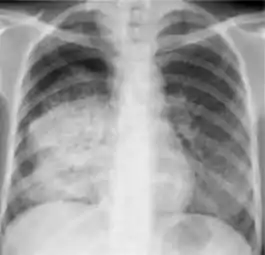

1. Infiltrate or consolidation - Opacification of airspaces within the lung parenchyma. Consolidation or infiltrate can be dense or patchy and might have irregular, ill-defined, or hazy borders.

Dense homogenous opacity in right, middle and lower lobe of primary pulmonary TB.

Chest x-ray showing patchy opacification on the upper right and mid-zone lung with fibrotic shadows, as well as bilateral hilar lymphadenopathy.